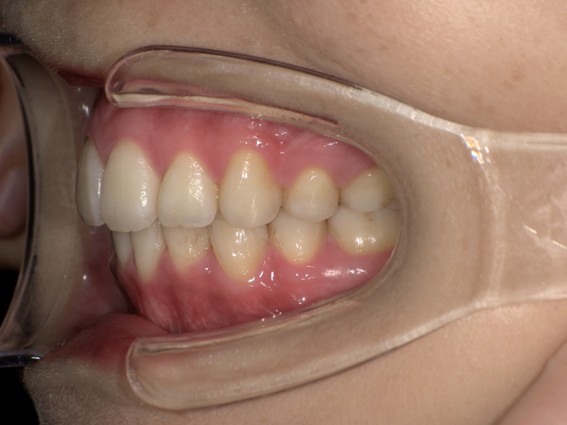

| 主訴 | 前歯が逆に噛んでいるところがある。歯のがたつき。 |

| 治療内容 | 表側ワイヤー矯正、4本抜歯を行いました。 |

| 治療費 | 880,000円+ダイレクトボンディング33,000円(税込) |

| 治療期間 | 30ヶ月 |

| 治療回数 | 30回 |

| 想定されたリスク | 歯根吸収、歯髄壊死、歯髄充血、歯肉退縮のリスクがありました。 |